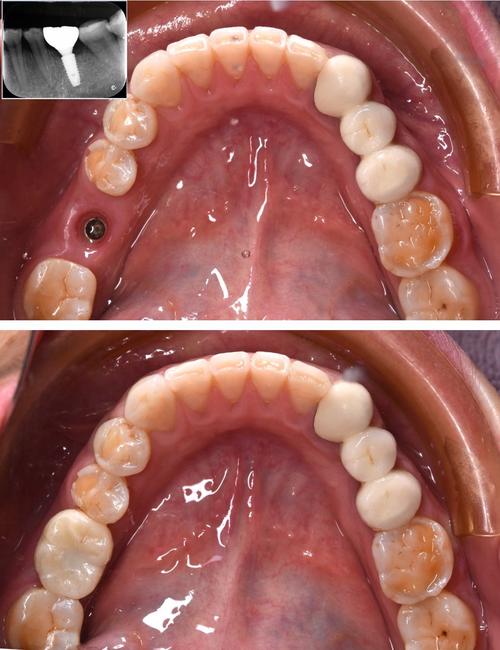

| 种植手术 | 局部麻醉下,在牙槽骨植入种植体(类似“人工牙根”),微创手术无需缝合,术后即可戴临时牙冠。 | 1-2 |

| 骨结合期 | 种植体与牙槽骨融合,期间避免咀嚼硬物,需定期复查。 | 3-6个月 |

| 牙冠修复 | 骨结合后,取模制作永久牙冠(全瓷冠、烤瓷冠等),佩戴并调整咬合,完成最终修复。 | 7-14 |